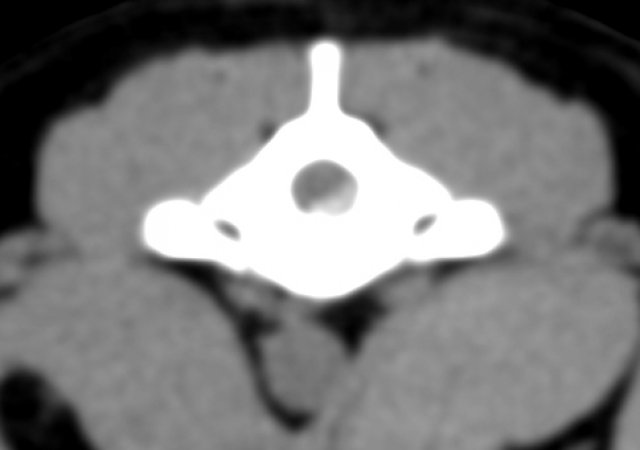

Durch Screening Methoden wie dem ED-Röntgen kann man Hinweise auf einen frakturierten Processus coronoideus medialis ulnae (FCP) bzw. eine Coronoiderkrankung, einen isolierten Processus anconaeus (IPA) oder Wachstumsstörungen von Radius (Speiche) und Ulna (Elle) sehen. Für eine sichere Diagnostik ist jedoch die Computertomographie (CT) das Diagnostikum der Wahl.

Wir führen in unserer Praxis sowohl CT Untersuchungen des Ellbogens, als auch eine arthroskopische Beurteilung dieses Gelenks durch.

Die minimalinvasive Arthroskopie ergänzt in der Diagnostik von komplexen Fällen das CT und bietet gleichzeitig die Möglichkeit, Erkrankungen wie einen FCP oder eine OCD (Osteochondrose des Humerus) minimalinvasiv zu operieren.

CT Bandscheibe Transversal